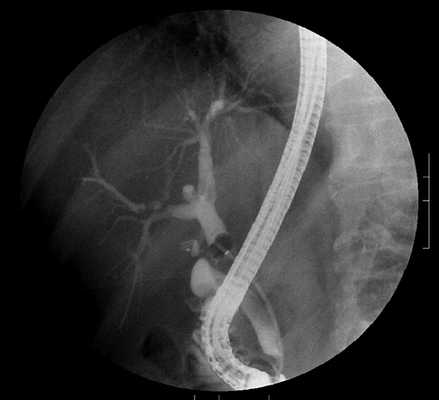

- ЭРХПГ. Эндоскопический инвазивный метод исследования используется для визуализации холедоха и желчных ходов, забора материала для гистологической диагностики (по показаниям). Вместо ЭРХПГ может назначаться чрескожная чреспеченочная холангиография.

Исследование подразумевает использование рентгеновского излучения и специальных компьютерных программ; полученные снимки имеют высокую детализацию, минимальное количество искажений и артефактов по сравнению с применяемыми ранее способами. До усовершенствования лучевой диагностики использовали эндоскопическую ретроградную холангиопанкреатографию (РХПГ). Метод и сегодня считается «золотым стандартом» в диагностировании камней, блокирующих желчные протоки, к нему есть свои показания. Из-за высокой инвазивности, риска осложнений, выраженного дискомфорта и высокой лучевой нагрузки в настоящее время РХПГ выполняют значительно реже, преимущественно, если планируется удалить небольшие конкременты, препятствующие оттоку желчи. Достоверность метода не может быть оспорена.

Камни в желчном пузыре на снимке ретроградной холангиопанкреатографии

РХПГ является альтернативным видом диагностики заболеваний желчевыводящих путей. Ретроградная холангиопанкреатография сочетает эндоскопические методы и лучевую диагностику. В результате сканирования видны конкременты, размер которых не превышает 1 мм. РХПГ позволяет оценить степень сужения желчного протока. В этом заключается преимущество данного метода перед магнитно-резонансной томографией. В остальных случаях врачи рекомендуют использовать МР-холангиографию.